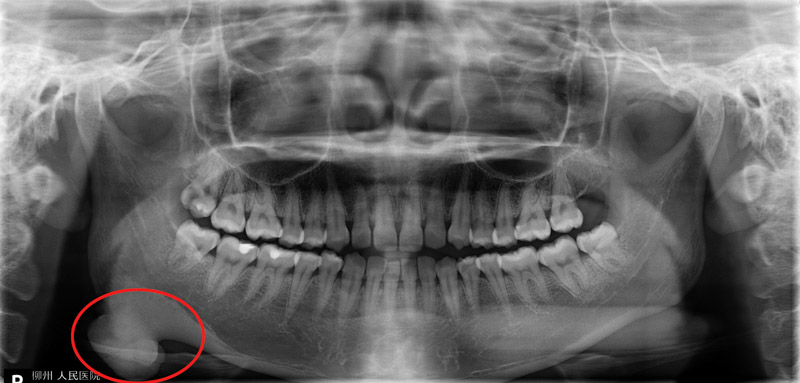

口腔科副主任醫(yī)師劉彥杰為唐女士做了仔細(xì)檢查,發(fā)現(xiàn)不是唐女士的臉越長越“方”,而是一顆骨性瘤子在作怪,這顆骨瘤正好就長在右側(cè)下頜角的位置。

下頜角截骨術(shù)(MAO)是一種對下頜角區(qū)進(jìn)行整形的手術(shù),主要適用于下頜角肥大的患者,手術(shù)從口內(nèi)做切口,用長柄擺動鋸在十分狹小的視野中將下頜角截除整形,多用于改善臉型,該類手術(shù)在柳州市開展尚屬首次。

為保障患者安全,在多次病例討論后,口腔科手術(shù)團(tuán)隊(duì)做了多次術(shù)前評估,并設(shè)計(jì)了精密的3D打印截骨導(dǎo)板。術(shù)中,劉彥杰醫(yī)生利用導(dǎo)板引導(dǎo)精確進(jìn)行截骨,順利從口內(nèi)將腫物切除。